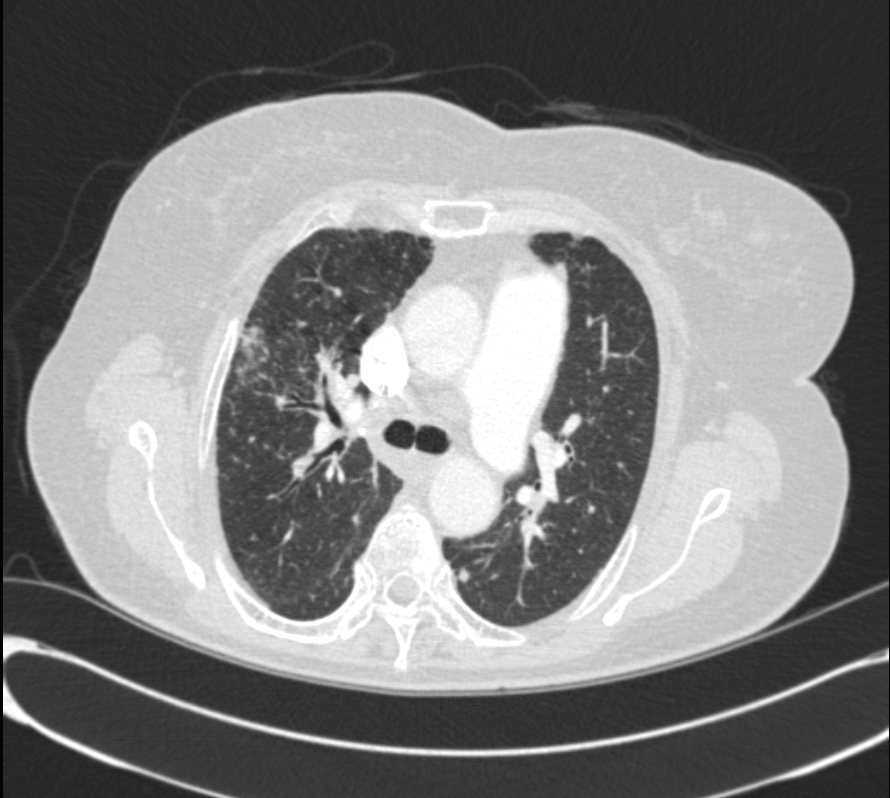

DOE  ÁּҷΠ evaluation  À§ÇØ ÃÔ¿µÇÑ  CXR ¹× chest CT ¼Ò°ßÀÔ´Ï´Ù.

* CXR °ú  chest CT  »çÁøÀÔ´Ï´Ù.

¶Ñ·ÇÇÑ ¿µ»óÀ» À§ÇØ f/u Áß¿¡ ÂïÀº »çÁøÀ» ÷ºÎÇÏ¿´½À´Ï´Ù.

l  Chest CT

Progression of multiple small nodules in both lungs, along peri-BV and ILS, dominant on RUL and RML. No significant change of several small LNs in both hilar and mediastinum.   COPD: diffuse bronchitis. LH enlarge and PAH.